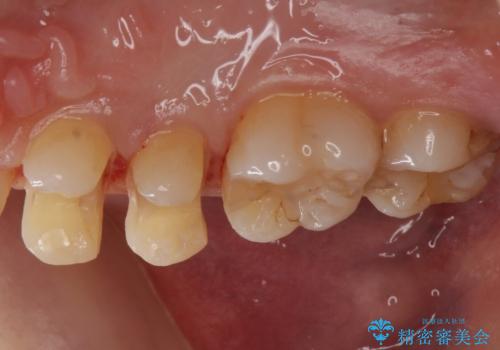

- 歯の健診にて来院。

レントゲンを撮った時にう蝕があったため、拡大鏡下でう蝕が残っていないか確認し

セラミックの詰め物(e-maxインレー)にて治療を行いました。